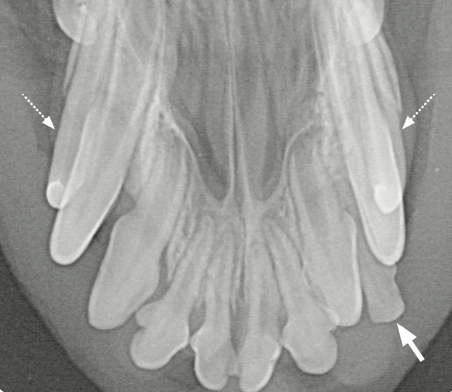

Hyperdontie: Ist eine Extraktion notwendig?

Wann ist eine Extraktion überzähliger Zähne notwendig? Das Röntgenbild kann Aufschluss geben, wie in diesem Fall bei einem Mischlingshund, 8 Jahre, männlich kastriert.

Differentialdiagnostisch sollten persistierende Incisivi – Milchzähne (▶️) ausgeschlossen werden. Sofern stomatologisch wie röntgenologisch keine Hinweise auf eine Zahnerkrankung vorliegen, kann der zusätzliche Zahn belassen werden. Allerdings wird ein Zuchtausschluss empfohlen.